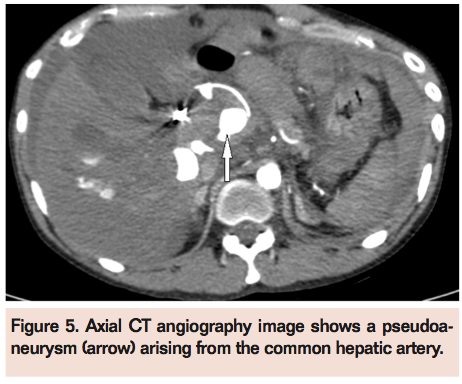

A digital subtraction angiography (DSA) was performed (Figure 3A) and the pseudoaneurysm arising from the right hepatic artery was embolized (Figure 3B) with two 0.18 coils (platinum fibered coils, Boston Scientific/Target Therapeutics) and he was discharged in a stable condition. Three days later, he presented with acute abdominal pain, pallor, and tachycardia. His hemoglobin level was 7.8 gm%. CTA revealed increased dilatation and dissection of the celiac trunk and common hepatic artery (Figure 4) associated with a right-sided perinephric hematoma. He was managed conservatively, given blood transfusions, and discharged on recovery. However, he presented 5 days later with acute abdominal pain, distension, tachycardia, and hypotension. He required intubation and inotropic supports in the intensive care unit. A repeat CT angiography showed aneurysmal dilatation of the celiac trunk and common hepatic artery and extension of the dissection associated with a large pseudoaneurysm (Figure 5). Repeat DSA was done on an emergency basis (Figure 6A) and the aneurysmally dilated common hepatic artery was embolized with 20% Histoacryl glue (Figure 6B). There was no filling of the pseudoaneurysm in the post-embolization angiogram. The patient improved and was discharged when he stabilized a few days later. He died at home a week later.